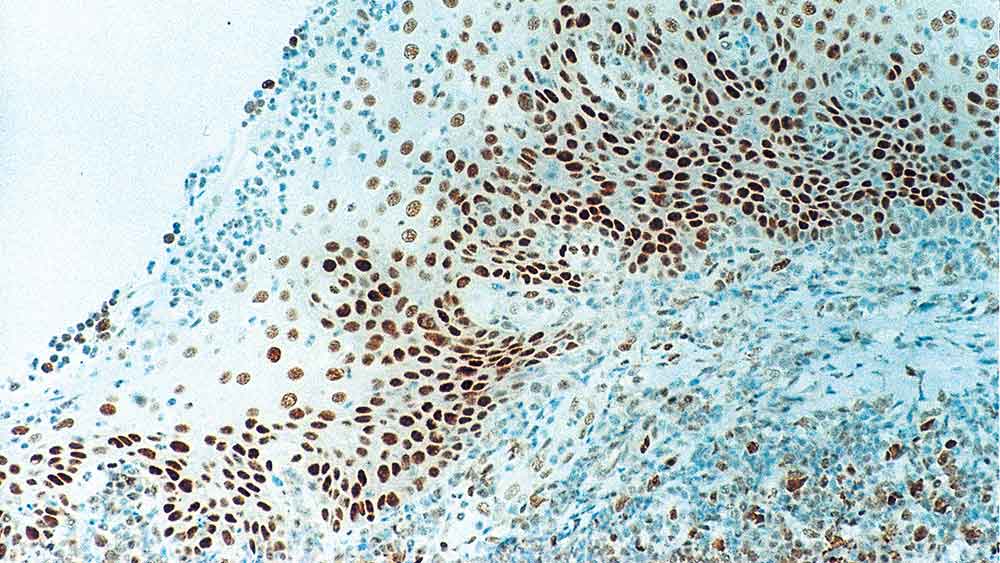

Human tonsil: immunohistochemical staining for Retinoblastoma Gene Protein. Note intense nuclear staining of epithelial cells. Retinoblastoma Gene Protein: clone 13A10

Retinoblastoma Gene Protein

NCL-L-RB-358 was raised to the N-terminal region of the Rb gene protein.